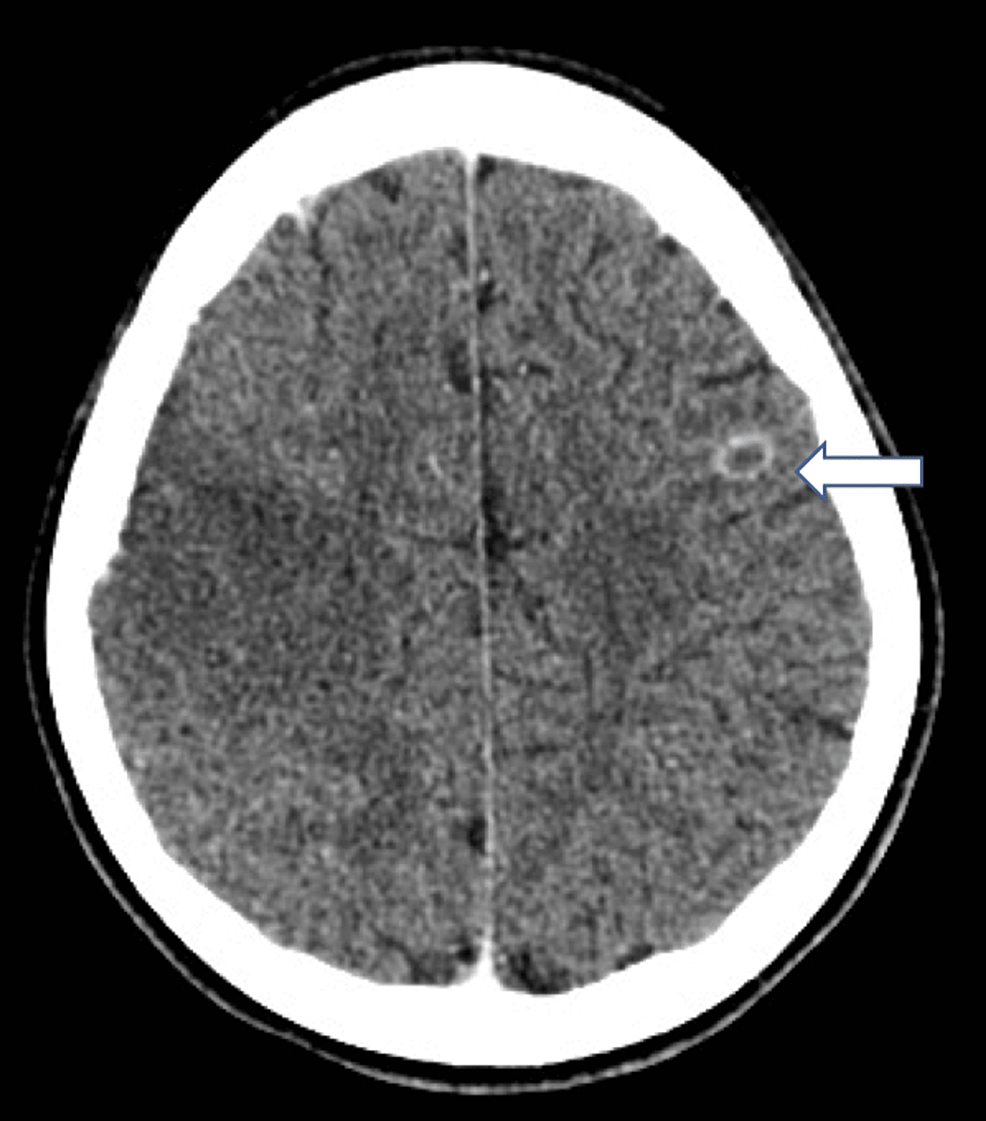

Figure 1 from Staphylococcus aureus Brain Abscess in an HIVInfected Patient Exposed to

Figure 1 from Staphylococcus aureus Brain Abscess in an HIVInfected Patient Exposed to Staph Infection Brain The spectrum of infection includes: This article explores four common types of brain infections, including their causes and symptoms. For example, endocarditis, a serious infection of the inner lining of your heart. Brain abscess is a focal collection within the brain parenchyma, which can arise as a complication of a variety of infections, trauma,. In this article, we review the. Staph Infection Brain.